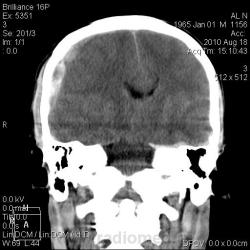

ЗЧМТ, правополушарная эпи-субдуральная гематома (четко не вижу), с дислокацией срединных структур мозга влево и аксиально, с компремированием боковых, преимущественно, правого бокового и третьего желудочков, САК, КТ-признаки набухания вещества головного мозга. Линейный перелом правой теменной и височной костей.

Я выставила линейный перелом правой теменной и височной кости с переходом на основание, эпи-субдуральная гематома 80 мл, САК, латеральная (13 мм) и аксиальная дислокация, отек вещества мозга, гемосинус основной пазухи. На операции оказалась эпидуральная гематома (но на мой взгляд, оценить ВСЮ гематому через трепанационное отверстие довольно сложно).

Перелом правой теменной кости, субдуральная гематома справа, смещение срединных структур и компрессия желудочков , особенно правого бокового и 3-его , гематома м/тканей справа+большая шишковидная железа, как я увидел на вскидку

Субдуральная гематома справа без сомнений. Слева незначительное количество крови субдурально.